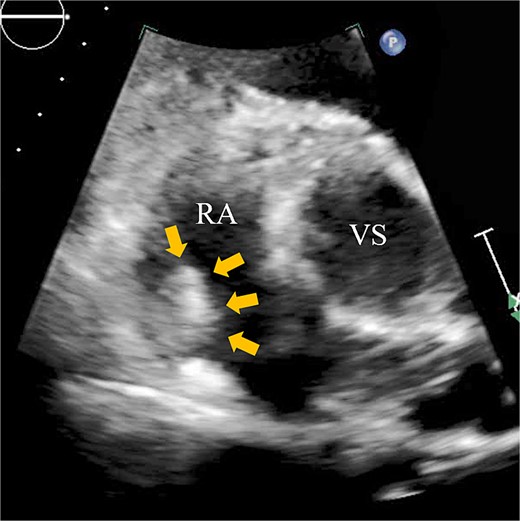

A 74-year-old male with a history of chronic atrial fibrillation (AF) for over 10 years, cardioembolic stroke, and cerebral hemorrhage, who had undergone LAA closure using the WATCHMAN device 1 year prior, was admitted after a follow-up contrast-enhanced CT scan revealed a 25-mm intracardiac mass in the right atrium (RA) (Fig. 1). After the WATCHMAN implantation, the patient was initially on direct oral anticoagulant (DOAC) but switched to dual antiplatelet therapy (DAPT) following the placement of a drug-eluting stent during percutaneous coronary intervention performed 9 months later. Transthoracic echocardiography revealed a left ventricular ejection fraction of 61% and a right atrial mass measuring 17 × 19 mm with slight mobility (Fig. 2). Despite anticoagulation therapy with heparin, the right atrial mass did not reduce in size. The patient decided to undertake surgical removal of the mass due to the potential risks of tumor or embolization. Additionally, contrast-enhanced CT showed a peri-device leak around the WATCHMAN device (Fig. 3). Considering the patient’s history of cerebral hemorrhage and the anticipated future cessation of anticoagulation therapy, we determined to perform WATCHMAN device explantation and LAA closure. Preoperative contrast-enhanced CT showed no thrombi attached to the WATCHMAN device and sufficient distance from the left circumflex artery (LCX) and the device (Fig. 4). We planned to remove the device by incising from the outside surface of the LAA. The Maze procedure was not performed because it was considered less effective due to the patient’s history of AF lasting more than 20 years and the presence of flat f-waves in lead V1 on the 12-lead electrocardiogram.

Transthoracic echocardiography showing a right atrial mass measuring 17 × 19 mm with slight mobility (arrows). VS, Valsalva sinus.